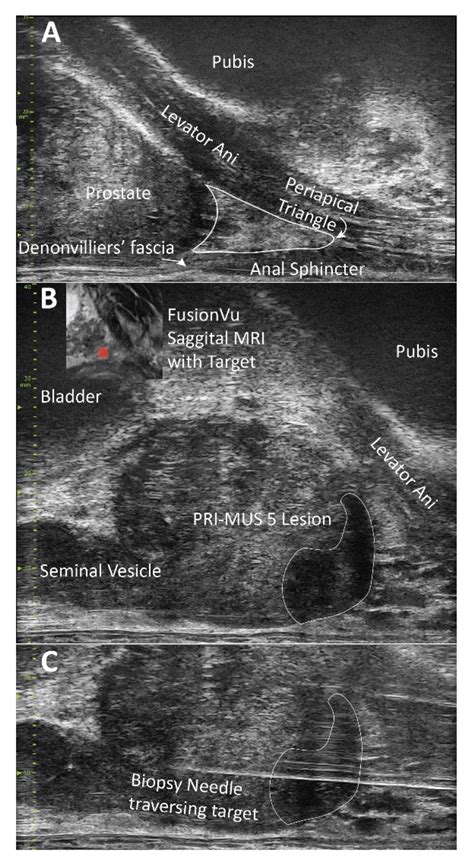

1. Imaging: An ultrasound probe is placed in the rectum to visualize the prostate gland on a monitor.

3. Sampling: Using a specialized grid or free-hand technique, the urologist directs a biopsy needle through the skin of the perineum and into the prostate to collect the tissue samples.

The integration of high-resolution MRI imaging with the transperineal biopsy technique represents a major leap forward in personalized medicine. By performing "targeted" biopsies, physicians can avoid unnecessary over-sampling of benign tissue and focus exclusively on suspicious areas. This reduces the number of needle passes required, further enhancing patient safety. As technology evolves, we are moving toward a future where prostate cancer detection is not only more accurate but also less invasive, leading to better outcomes for men worldwide.